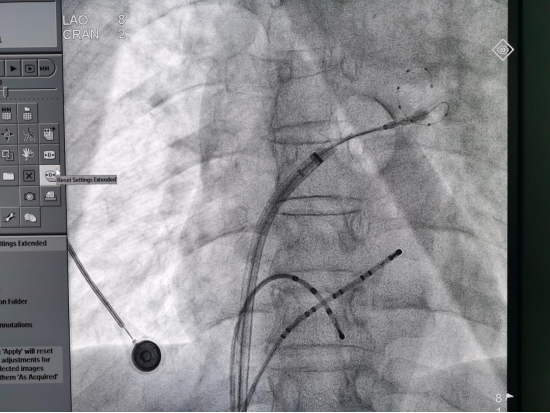

2021年12月19日,市第一人民医院心血管内科二病区开展川陕甘结合部首房颤冷冻消融术自此,开启了医院房颤治疗“冷冻”新时代。

一切准备就绪后,12月19日上午,大内科副主任邓小军、心血管内科二病区副主任刘盼带领起搏与电生理团队经右股静脉行房间隔穿刺后,将冷冻球囊送至肺静脉,有效阻断了异常的电传导,从而完成稳定的肺静脉隔离,让患者过度躁动的心“冷静”下来。术后,患者身体恢复良好。

“该新技术采用液态制冷剂吸热蒸发,带走肺静脉“漏电”处的组织热量,“冻死”病变组织从而达到治疗房颤的目的。相对于传统射频消融方法,冷冻消融技术具有更安全、快速、有效、复发率低、患者耐受性好等优势,目前已经成为国内心脏中心首选非药物治疗方法。”刘盼副主任介绍到。

冷冻球囊导管消融术是近几年来治疗房颤的一的微创治疗技术。其采用冷冻的能量,通过温度骤降和温度复温的过程,达到组织快速坏死,甚至是不可逆的坏死,使房颤得以消除。